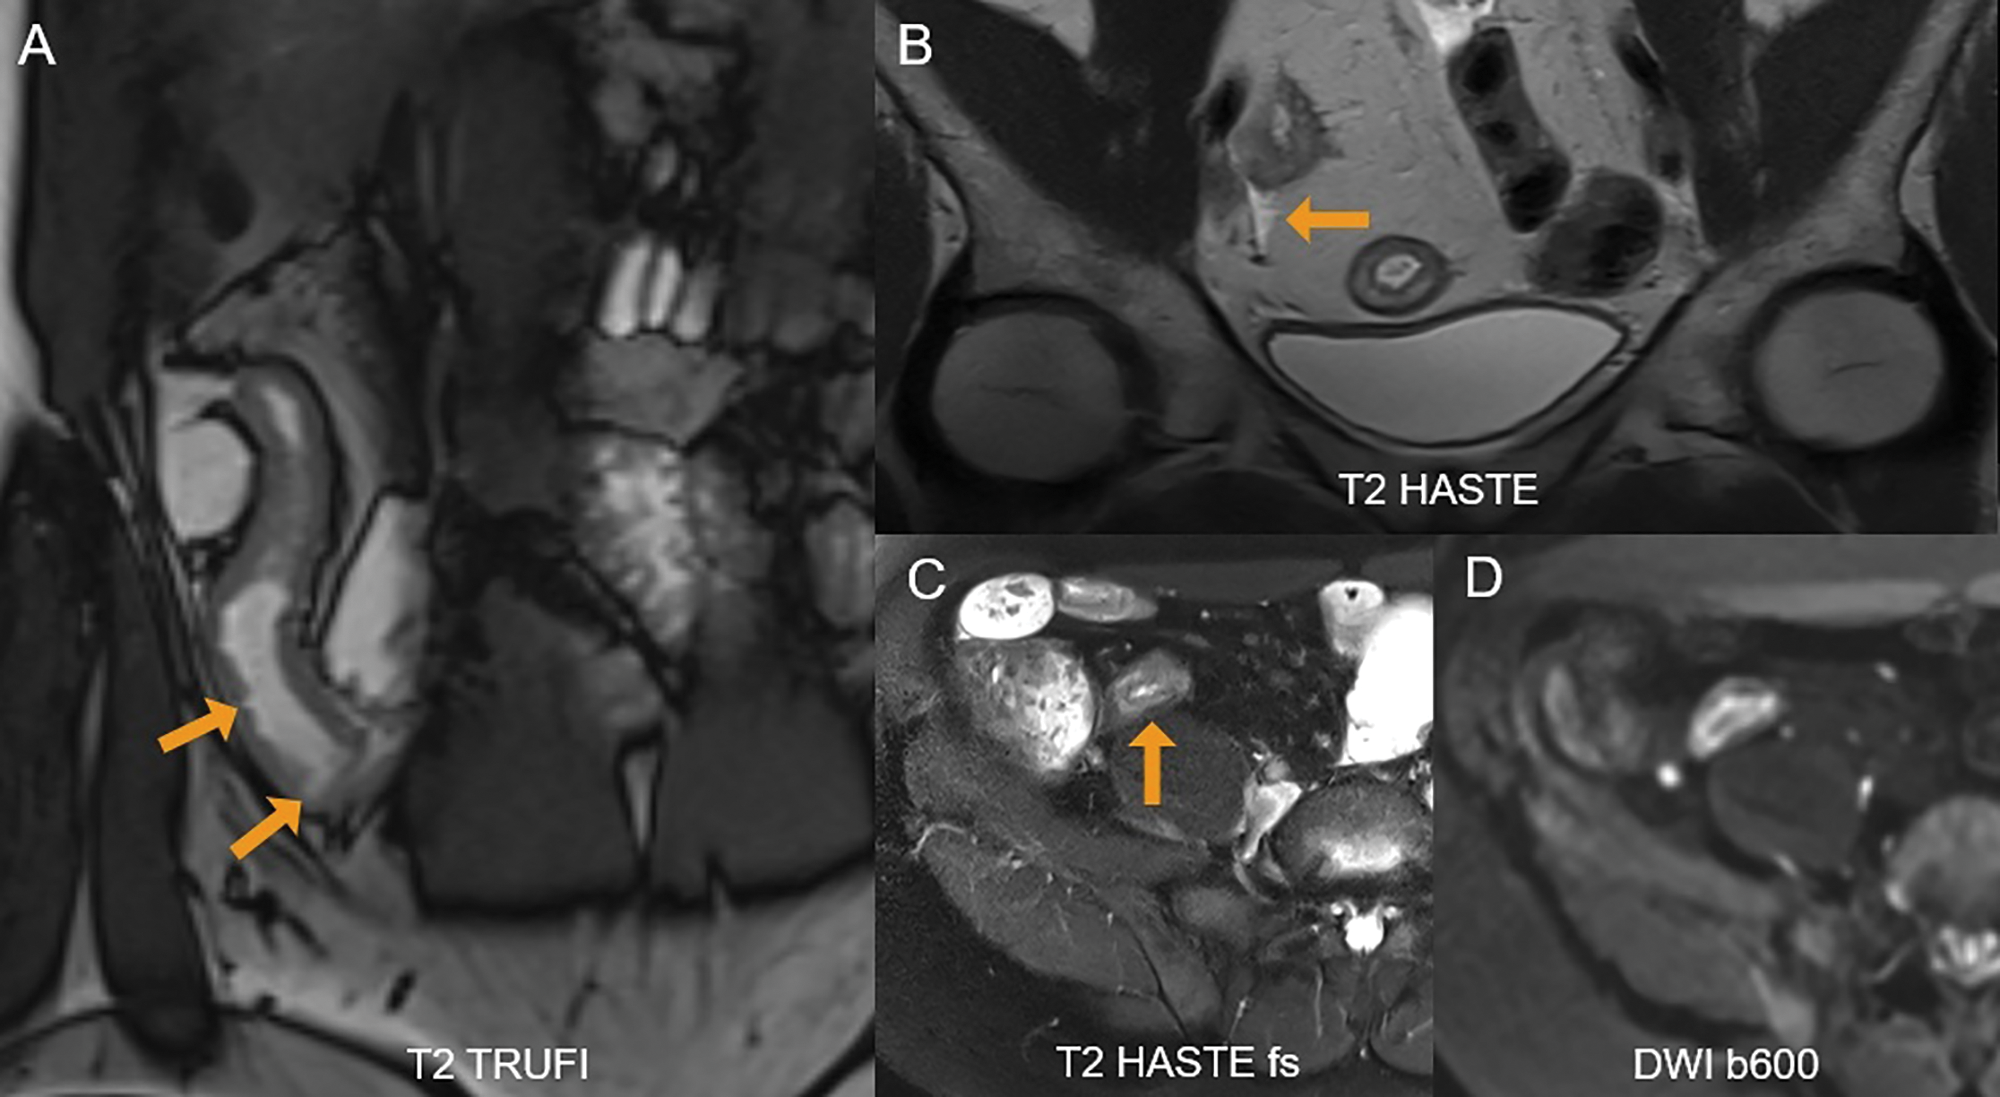

On MRE, active Crohn’s disease is characterized by (1) bowel wall thickening (> 3 mm in distended loops), (2) high mural T2 signal intensity indicating oedema, (3) increased vascularization reflected by mural hyperenhancement and engorged vasa recta (“comb sign”), (4) ulcerations visible as small mural defects, and (5) perimural inflammation seen as high T2 signal intensity in the mesenteric fat (Figure 1). On IUS, the key features include (1) bowel wall thickening (>3 mm), (2) loss of mural stratification due to oedema, (3) increased (extra)mural vascularity on colour Doppler, (4) ulcerations, and (5) hyperechoic mesenteric fat and/or free fluid adjacent to the inflamed bowel segment (Figure 2) [1, 4].

Figure 1

A 36‑year‑old female with active Crohn’s disease. (A) Coronal T2 TRUFI image shows ulcerations in the inflamed terminal ileum as focal intraluminal surface defects (arrows). (B) Perimural inflammation with adjacent free fluid is seen (arrow). (C) Fat‑suppressed T2‑sequence demonstrates high mural T2‑signal in the terminal ileum (arrow). (D) The inflamed segment also shows restricted diffusion.